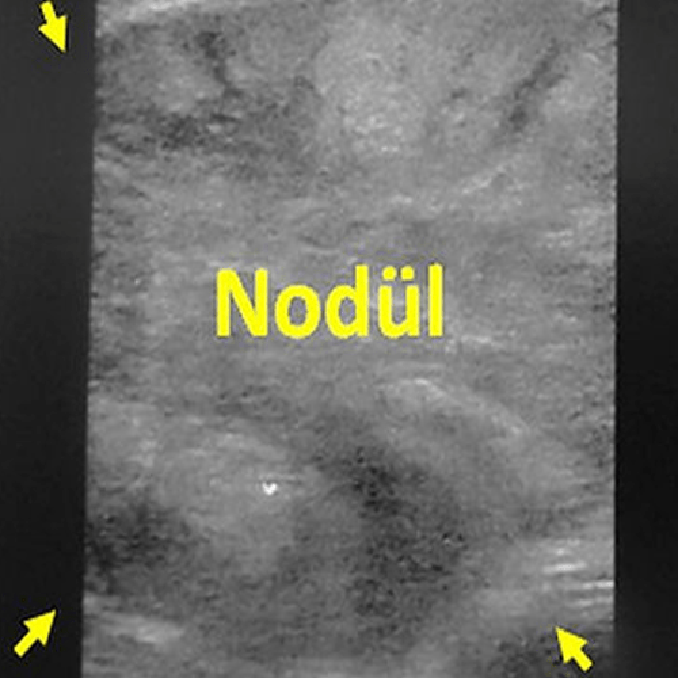

Önce, ultrason ile tiroiddeki ablasyon yapılacak nodül tesbit edildilir. Daha sonra, ciltte giriş yeri lokal anestezi ile uyuşturulur ve mikrodalga iğnesi ultrason rehberliğinde nodüle yerleştirilir. Bu aşamada, cihaz çalıştırılarak ablasyona başlanır. Ablasyon sırasında, nodülün yerleşimi ya da büyüklüğüne göre, iğne ya sabit tutulur ya da nodül içinde değişik yönlere ilerletilerek nodülün her tarafının etkilenmesine çalışılır (Moving shot tekniği). Lazer ve radyofrekans ablasyonda olduğu gibi, mikrodalganın ısıttığı alanlar da ultrasonda beyaz olarak görülür. İşlem bittikten sonra mikrodalga iğnesi çekilir ve hasta birkaç saat gözlendikten sonra taburcu edilir.

Tiroid bezinin istmus bölgesinde 72x53x47 mm dev nodülü olan 70 yaşında kadın hastamızda nodüle ultrason eşliğinde mikrodalga ablasyonu uygulandı. Bir yıl sonra hastanın boyun şişliği ortadan kalkmış ve ultrasonda nodülde %90’dan fazla bir hacim azalması izlenmiştir.”